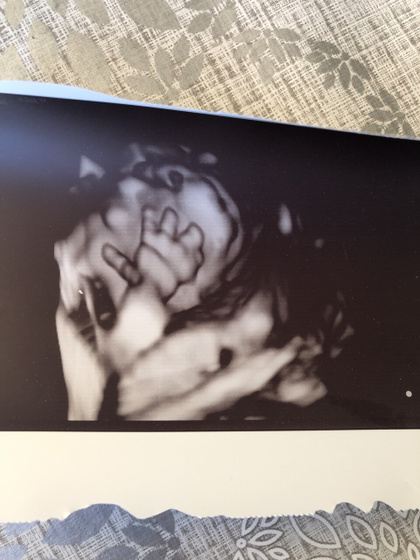

Слава богу все хорошо??наш сынок(а это уже точно) вырос) вес 232 грамма, шевелиться во всю?

Узистка не удивлена, почему он не мог поймать сб, она даже его еле словила!

Ну и бедренная кость на 17,5 недель.

В пределах нормы, но коротковата. Но это меня не расстроила, тк с дочей столкнулись с этим. Даже к генетику направляли. А оказалось особенность строения. Да и мы не высокие с мужем) личико прятал, да и вообще сам как егоза был??

Боже эти пальчики ??? сладкий тьфу тьфу расти кнопка